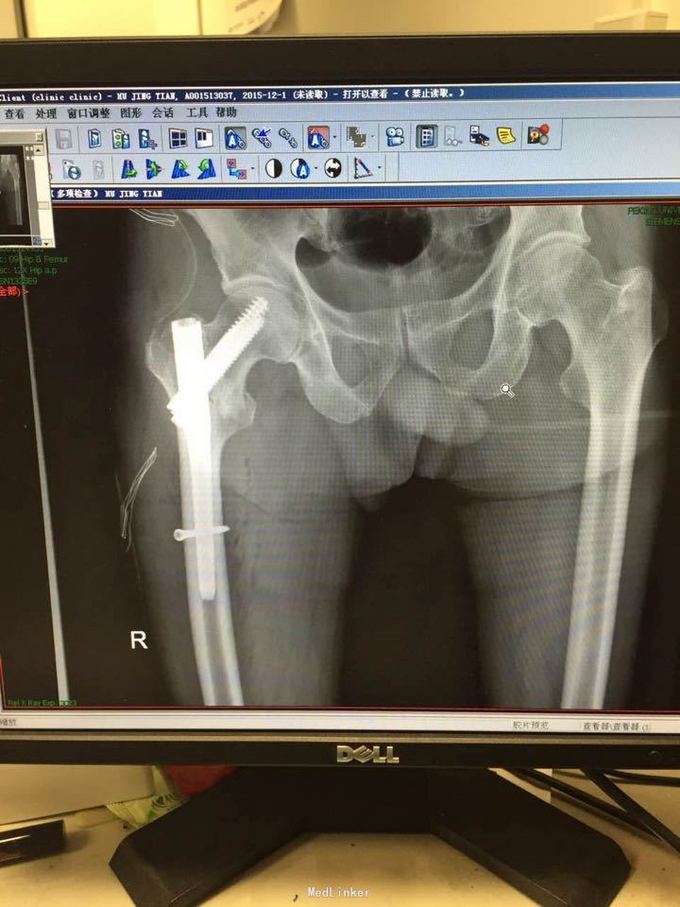

诊断:右侧股骨粗隆间骨折 治疗:完善术前检查,持续皮牵引,择期行闭合复位内固定术(防旋型股骨近端髓内钉(PFNA)内固定方法),术后复查X线

老年性股骨粗隆间骨折的I临床发病率逐年上升。股骨粗隆问骨折严重威胁老年人身心健康和生活质量。保守治疗卧床时间较长.易引起褥疮、肺炎等并发症,死亡率极高;即使患者骨折愈合,多残留髋关节畸形,严重影响活动能力。早期手术内固定可减少此类并发症,降低死亡率和病残率。因此,对其治疗方法的选择及疗效评价意义重大。通常采用动力髋螺钉(DHS)、Gamma钉、防旋型股骨近端髓内钉(PFNA)3种内固定方法。其中为,PFNA可明显缩短手术时间,术中损伤小,术中、术后发症较低及骨折愈合时间短。PFNA治疗老年骨质疏松性股骨粗隆间骨折较Gamma钉和DHS具有坚强内固定的优势,对控制骨折端的旋转和防止钉端所致的股骨近端骨折并发症等均提供了可靠的保证,是治疗老年骨质疏松性股骨粗隆间骨折的一种较合理有效方法.可以作为优先考虑的疗法。